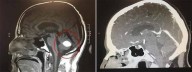

Milagre: Tumor cerebral de padre desaparece logo antes de ele ser operado